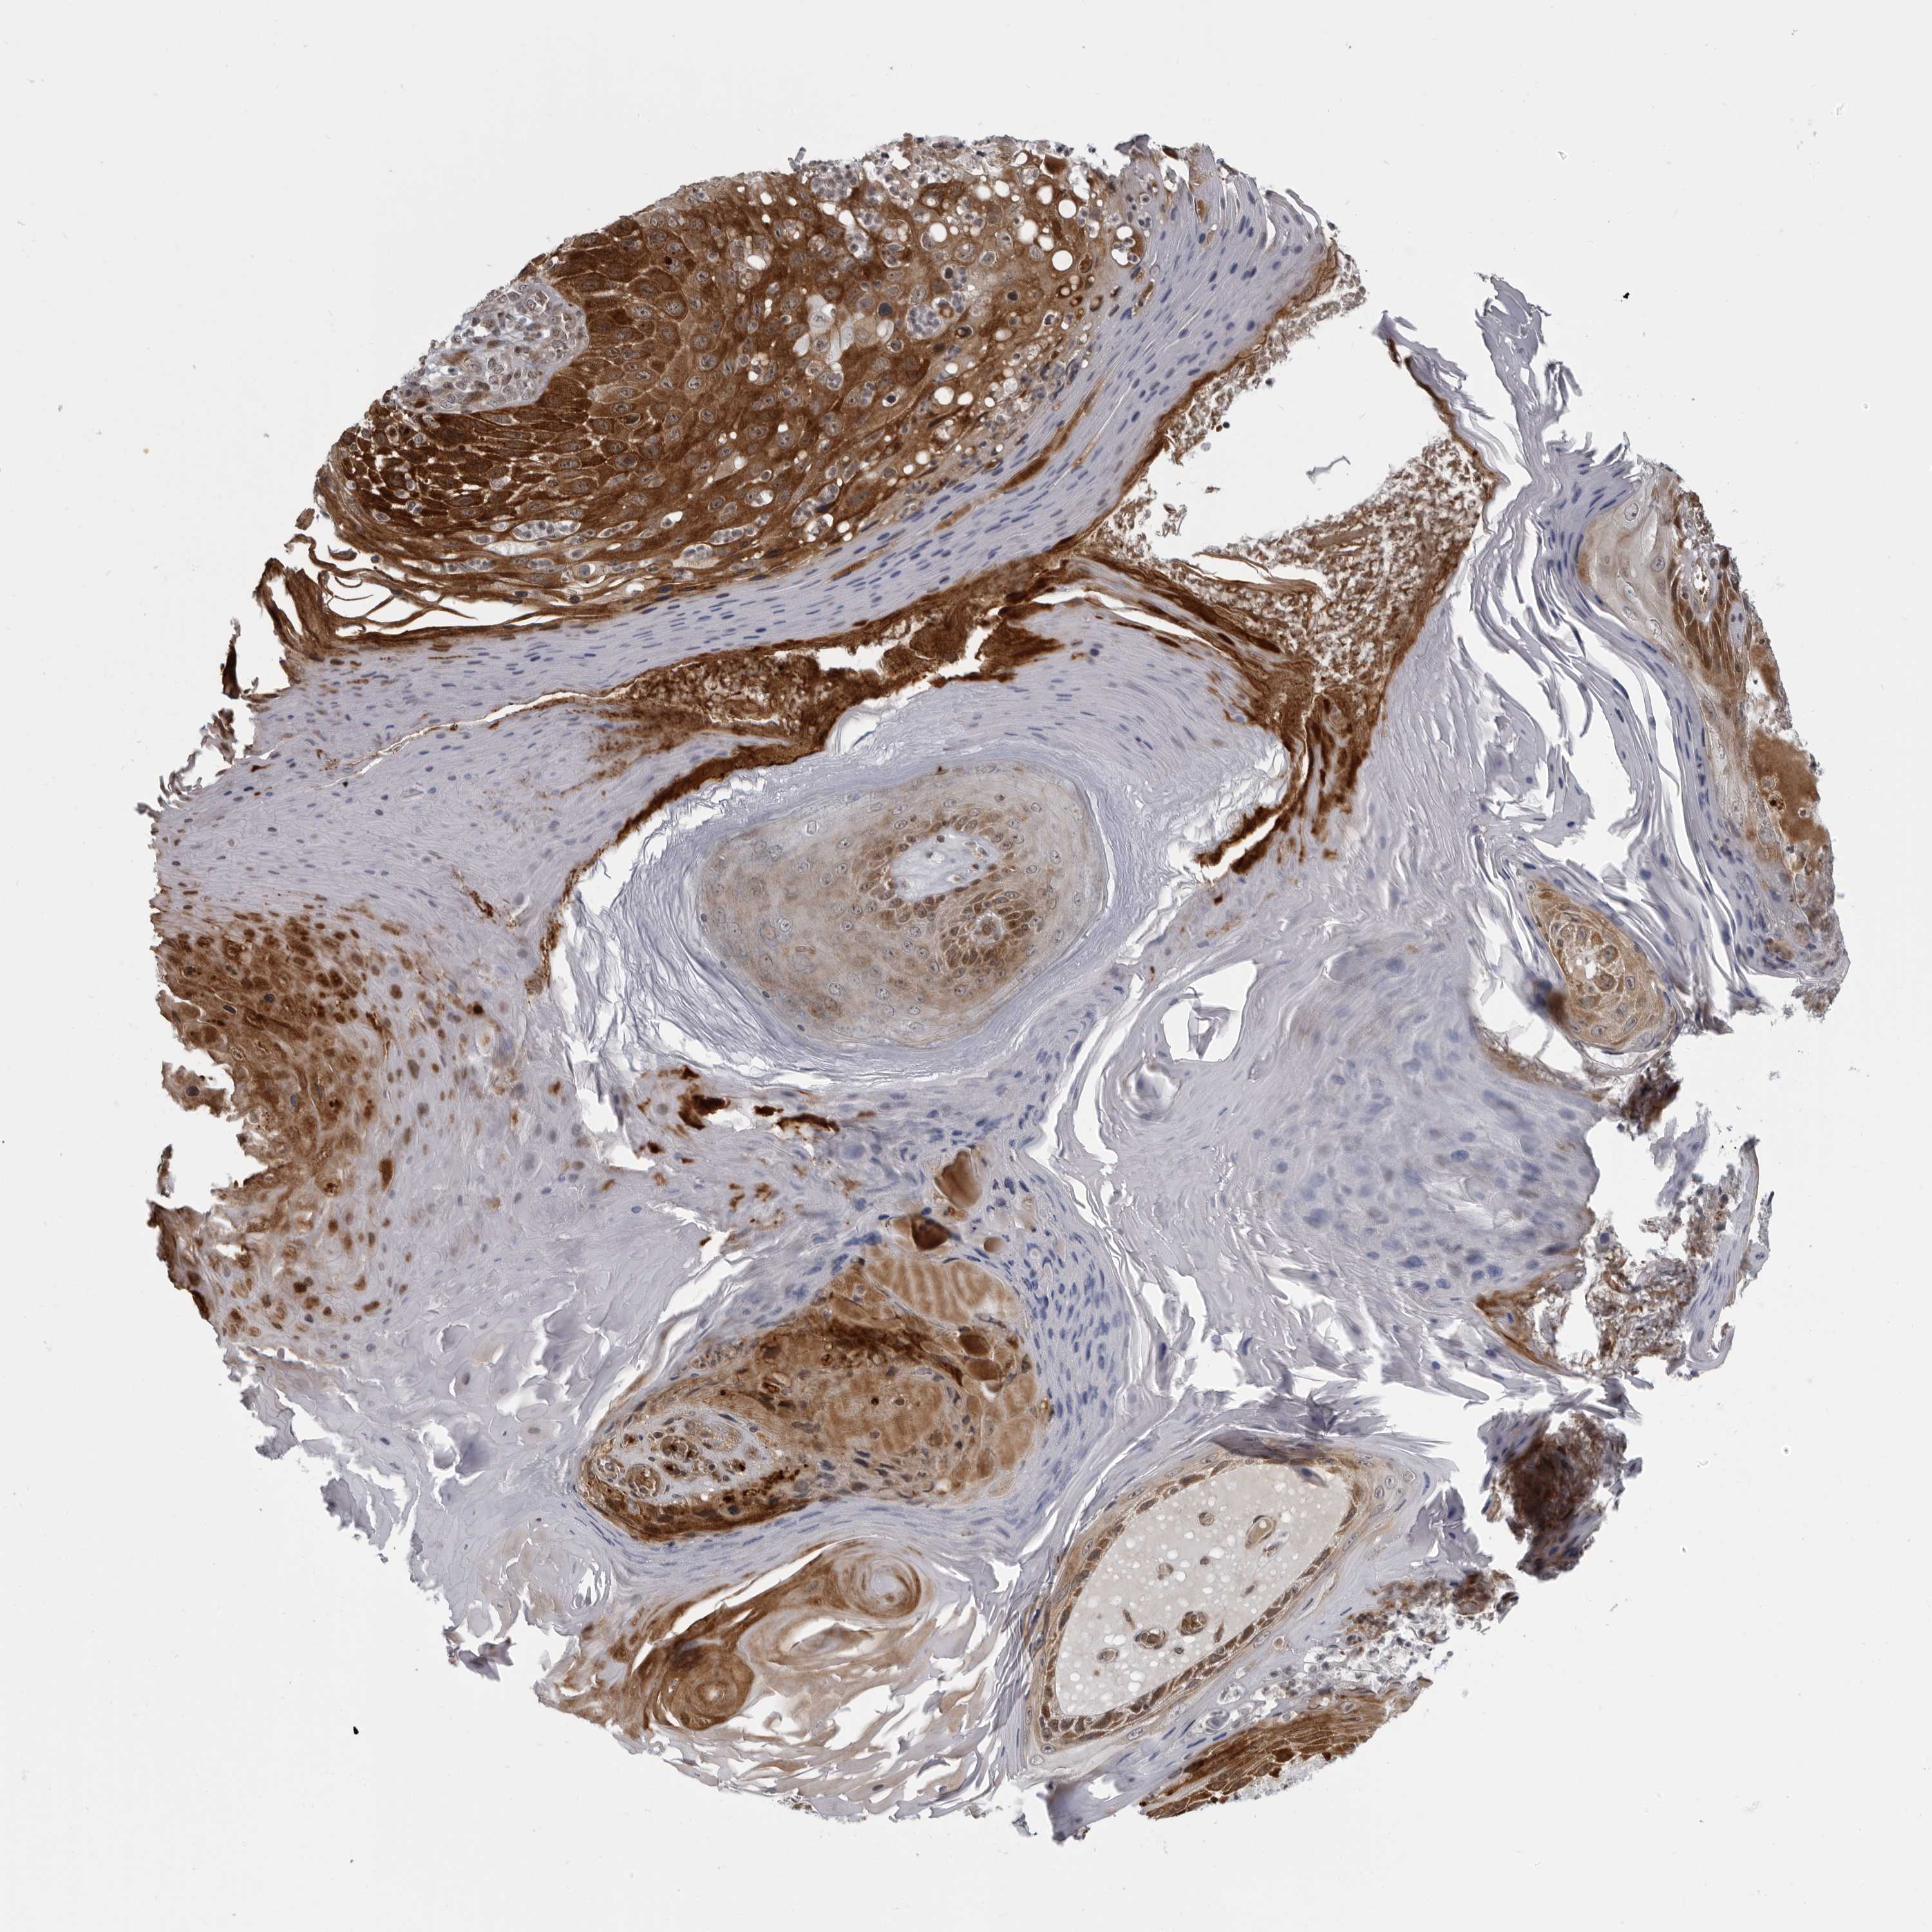

SKIN CANCER - Protein expressioni

A mouse-over function shows sample information and annotation data. Click on an image to view it in a full screen mode. Samples can be filtered based on level of antibody staining by selecting one or several of the following categories: high, medium, low and not detected. The assay and annotation is described here.

Antibody staining in the annotated cell types in the current human tissue is reported as not detected, low, medium, or high, based on conventional immunohistochemistry profiling in selected tissues. This score is based on the combination of the staining intensity and fraction of stained cells.

Each image is clickable and will lead to virtual microscopy that enables deeper exploration of all samples and also displays staining intensity scores, fraction scores and subcellular localization as well as patient and tissue information for each sample.

Antibody CAB025497

Staining

Medium

Strong

75%-25%

Cytoplasmic/membranous

Squamous cell carcinoma, NOS